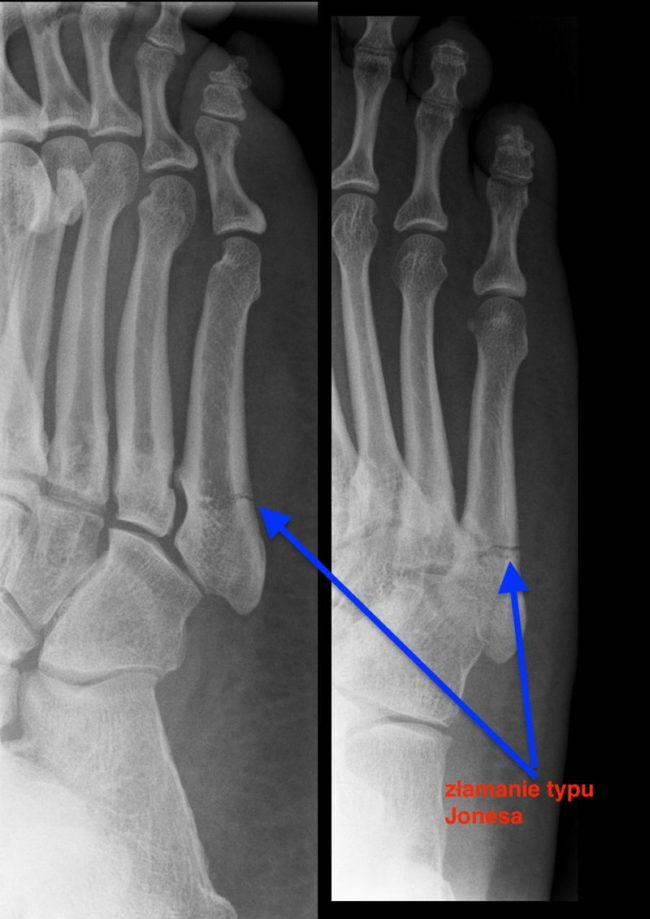

Zmęczeniowe uszkodzenia kości (cz.2) Zapraszam do lektury drugiej części tekstu na temat uszkodzeń (złamań) zmęczeniowych kości. W materiale pojawią się ważne aspekty tego problemu: badania diagnostyczne złamań zmęczeniowych, ocena stanu kości i leczenie urazów, oraz powrót do treningu po zakończonej rekonwalescencji. Wizyta pacjenta z podejrzeniem uszkodzenia zmęczeniowego kości W większości przypadków historia problemu pacjenta zaczyna…